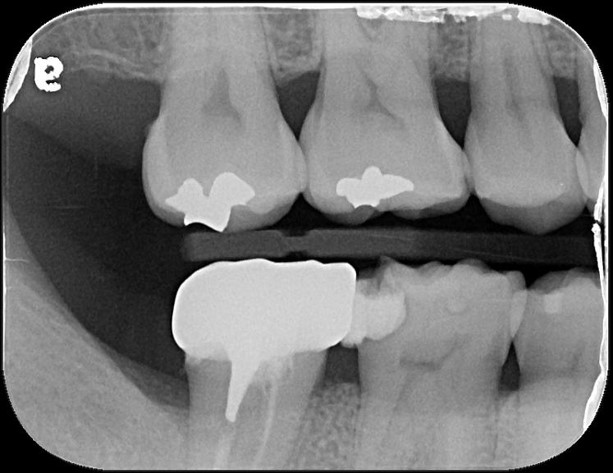

治療前,嚴重蛀牙,咬頭受損

蛀牙未到牙髓

冠塊體體製備